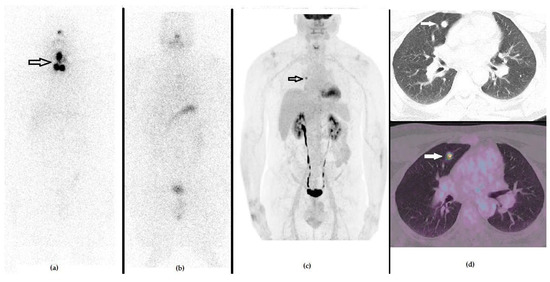

Figure 4. A 49-year-old male that previously underwent a thyroidectomy plus CND and 1 cycle of RAI due to PTC (pT3a N0 R0). The first panel represents the post-RAI 131I-WBS, showing the residual iodine-avid tissue in the anterior cervical region. (a) One year after RAI, he presented with an increased value of stimulated Tg serum level (i.e., 89 ng/mL), in spite of negative 131I-WBS (b) and no morphological signs of relapse at neck US or CXR. PET/CT with 18F-FDG demonstrated a focus of increased tracer uptake in the right lung, as evident by whole body (c) and axial CT (d, upper raw) and fused PET/CT ((d), lower raw) slices. The patient underwent surgery and histology was positive for PTC lung metastasis.